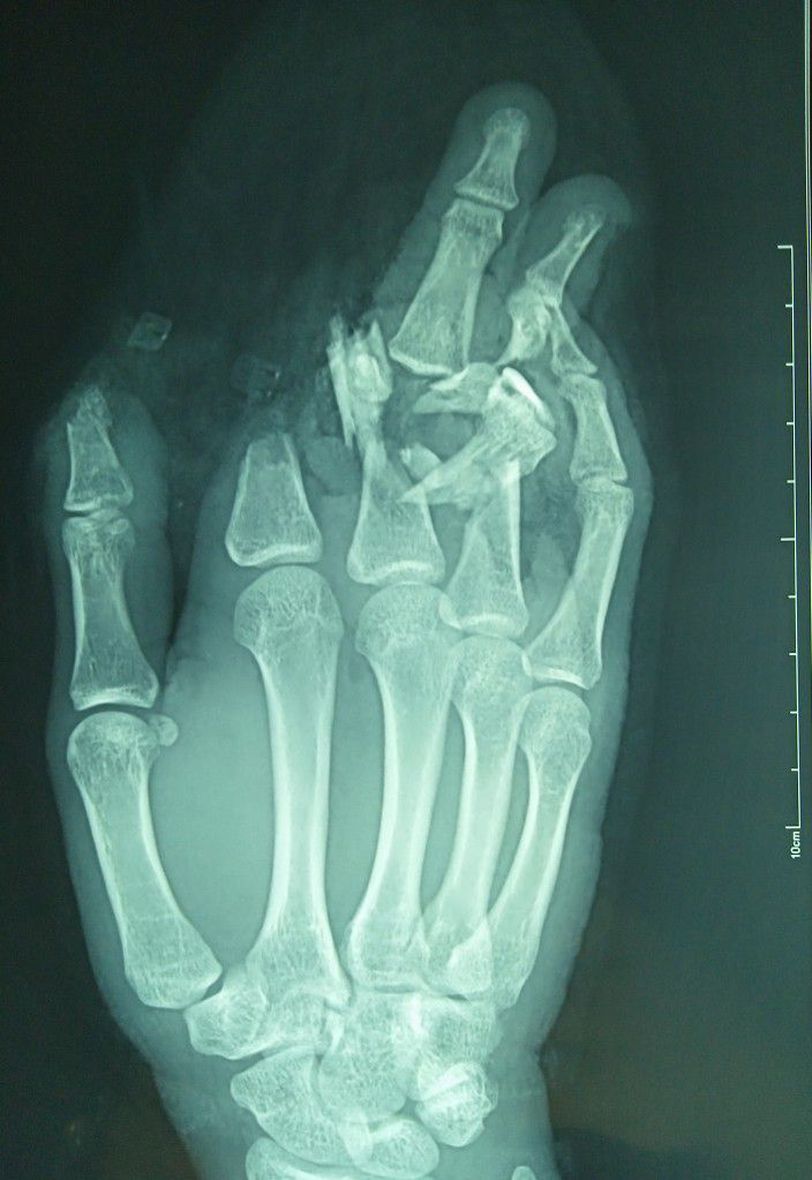

Industrial injury